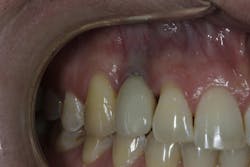

- Open contacts due to tooth migration, and cervical margin discrepancies in gingival height4 (figure 3)